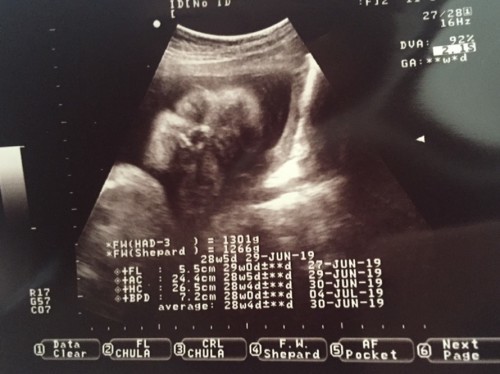

แม่ๆบ้านไหนซาวเห็นหน้าตัวเล็กบ้างค้ะ รู้เพศหรือยัง แม่บ้านนี้กำหนดคลอด2กค62 28วีค5วัน ซาวกี่รอบก็เพศชาย ขอดูแม่ๆที่คลอดน้องเดือนกรกฎาคมเหมือนกันหน่อยจ้า

วันนี้มีนัดซาวอีกรอบ หนที่แล้วน้องคว่ำหน้าอดเจอหน้าเลย 😁ผชค่ะ 15กค